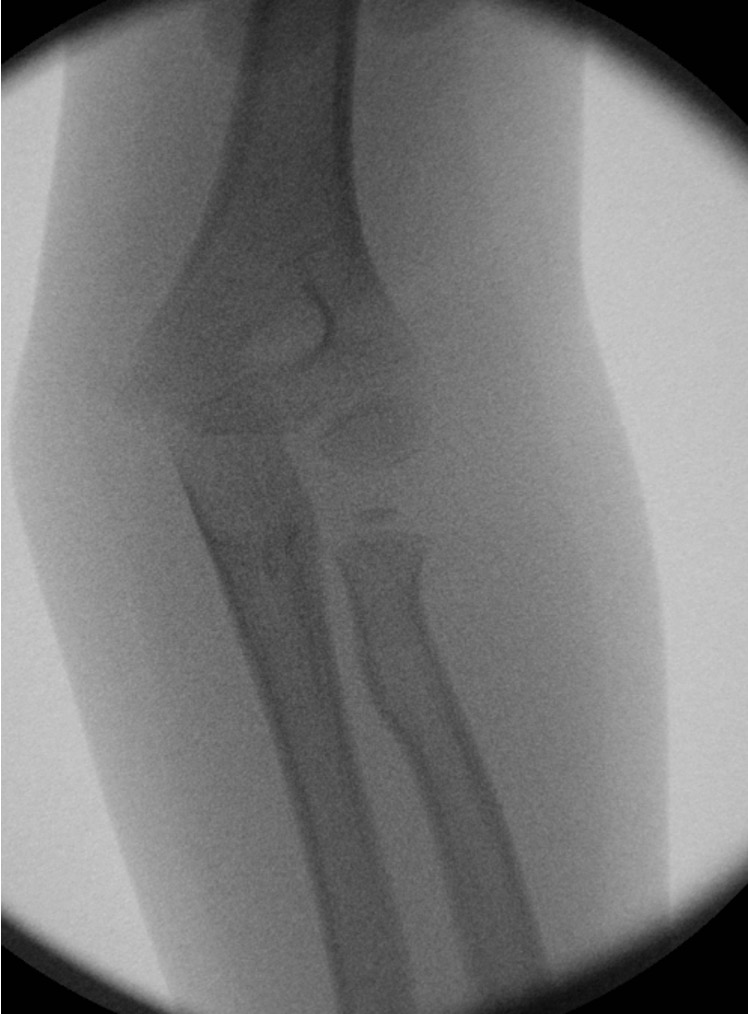

Percutaneous K wire

Technique

Pronate arm to protect PIN

- insert into fracture site

- lever fracture into reduced position

- then drive into opposite cortex